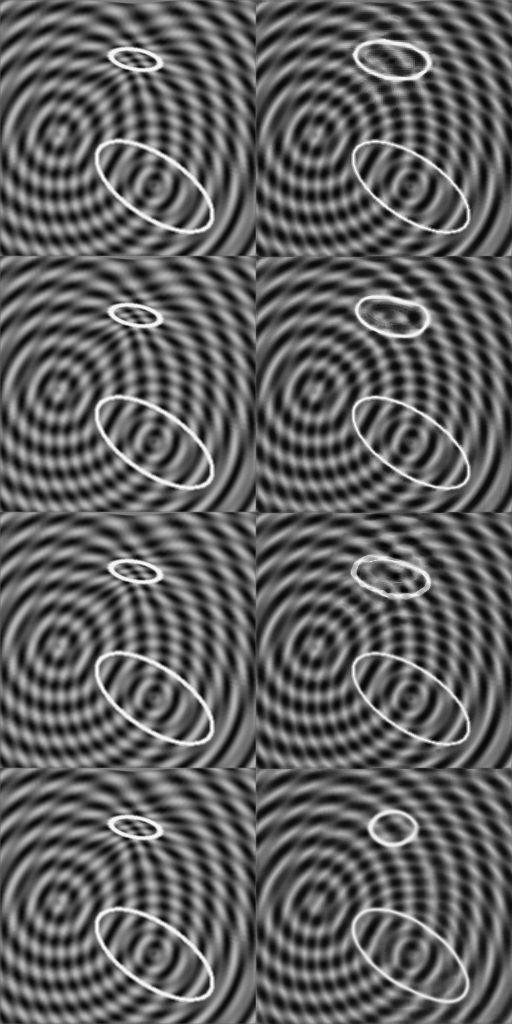

The purpose of weakly supervised algorithms is to overcome the need for pixel-wise labels and the human bias within these labels. In order not to be affected by this human bias, we designed a synthetic data set for the evaluation of our method. Two ellipses e1subscript𝑒1e_{1} and e2subscript𝑒2e_{2} are present in the image, one larger than the other and both with variable contour thickness, origin and orientation. The background is structured in concentric waves with two variable origins and variable wave length; this provides a higher level of complexity. Images of the healthy group \mathcal{H} keep this structure. If the image is deformed such that the smaller ellipse e1subscript𝑒1e_{1} shrinks to an even smaller ellipse, the background is also deformed. Images with this characteristics belong to the diseased group 𝒫𝒫\mathcal{P}. Implementation details are provided in the supplementary material.

In Figure 4, exemplary images of the two sets \mathcal{H} and 𝒫𝒫\mathcal{P} are shown. The pixel-wise ground truth (GT𝐺𝑇GT) is known by definition. We generate a training set of 2000 images of each class, and a validation and a test set with 200 images of each class.

Refer to caption(a)Refer to caption(b)Refer to caption(c)Refer to caption1-1

Figure 4: Images (a) and (b) show exemplary images of the sets \mathcal{H} and 𝒫𝒫\mathcal{P} respectively. Image (c) corresponds to the ground truth given by the difference (a) - (b).

In Figure 5, exemplary real images rp𝒫subscript𝑟𝑝𝒫{r_{p}\in\mathcal{P}} of the synthetic dataset with the corresponding artificial images ahsubscript𝑎{a_{h}\in\mathcal{H}} of the different methods are shown. Our method provides the most accurate difference map d𝑑d. The results of FP-GAN are good as well, but the method fails to generate a proper unshrunken ellipse e1subscript𝑒1e_{1}. VAE and VAGAN fail to generate an accurate image of class hh, resulting in a difference map not close to the ground truth. For visualization, we omit the StarGAN method since it is outperformed by its extension FP-GAN.

Refer to captionRefer to captionInput rpsubscript𝑟𝑝r_{p}Refer to captionRefer to captionOutput ahsubscript𝑎a_{h}Refer to caption11100|GT|𝐺𝑇|GT|Difference |d|𝑑|d|Input rpsubscript𝑟𝑝r_{p}Output ahsubscript𝑎a_{h}|GT|𝐺𝑇|GT|Difference |d|𝑑|d|DeScarGANFP-GANVAGANVAE

Figure 5: Visualization of the results of our DeScarGAN, FP-GAN, VAGAN and VAE for two samples of the synthetic dataset.